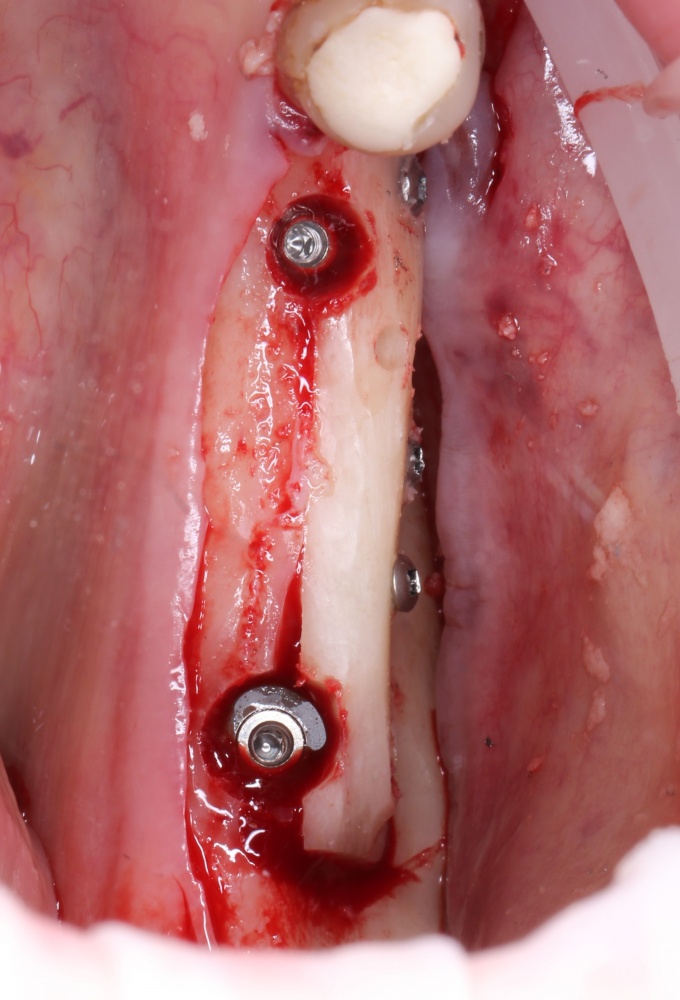

Простой. Надежный. Дешевый. Способ остеопластики.